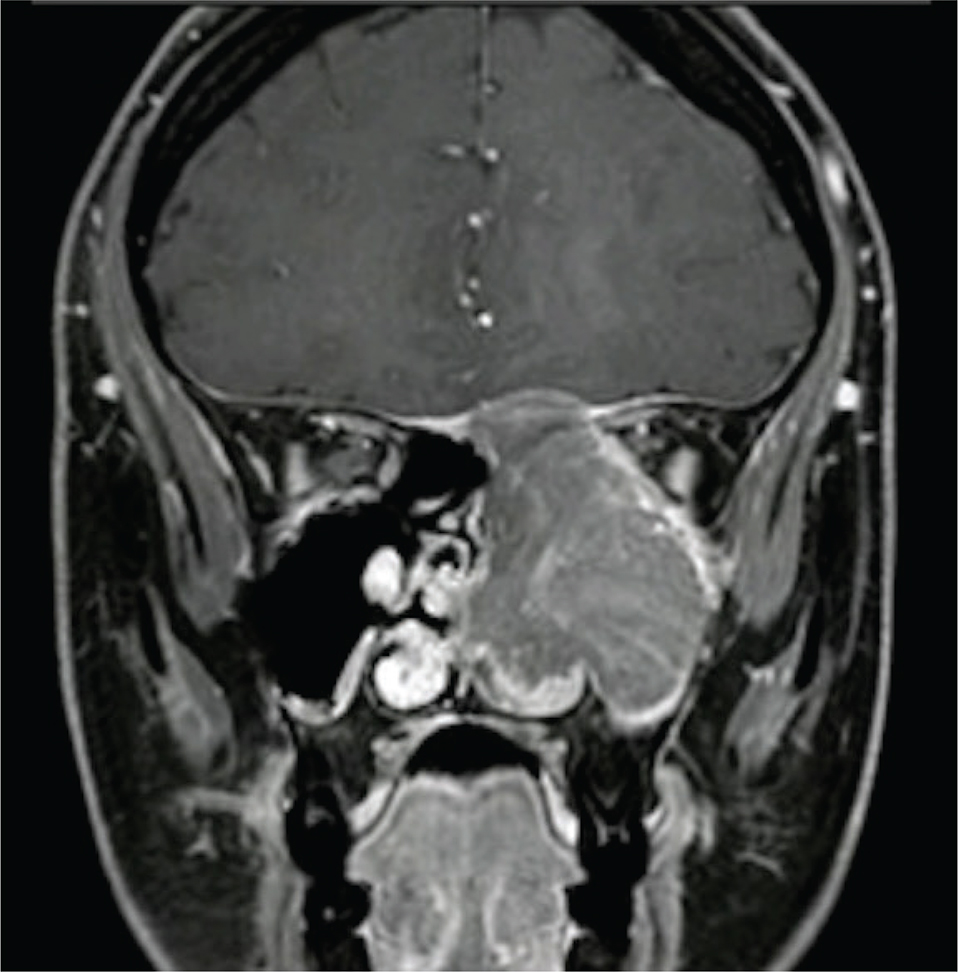

A 29-year-old patient in week 26 of gestation consulted for left hemicraneal headache, retroocular pain, nasal congestion, and moderate recurrent epistaxis. On examination, a mass in the left nasal fossa in contact with nasal conchae, left eye proptosis with limitation for abduction, and diplopia with supraduction and abduction were evident (Fig. 1). A biopsy was performed with pathology compatible with high-grade large cell neuroendocrine carcinoma. Orbit and cranial Magnetic Resonance Imaging (MRI) revealed an extension of the lesion to the left orbit, maxillary sinus, and left pterygopalatine fossa, with localized dural enhancement (Fig. 2). No evidence of metastatic involvement was found in further images, making surgical treatment the first option.

Fig 2

Fig. 2. MRI presenting the extension of the tumor in the left orbit, maxillary sinus, left pterygopalatine fossa, and localized dural enhancement.